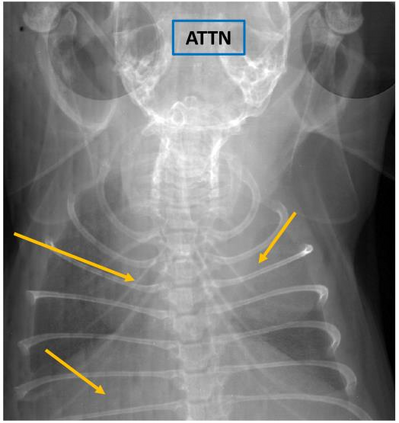

Low-dose computed tomography (LDCT) is the current standard for lung cancer screening, yet its adoption and accessibility remain limited. Many regions lack LDCT infrastructure, and even among those screened, early-stage cancer detection often yield false positives, as shown in the National Lung Screening Trial (NLST) with a sensitivity of 93.8 percent and a false-positive rate of 26.6 percent. We aim to investigate whether X-ray dark-field imaging (DFI) radiograph, a technique sensitive to small-angle scatter from alveolar microstructure and less susceptible to organ shadowing, can significantly improve early-stage lung tumor detection when coupled with deep-learning segmentation. Using paired attenuation (ATTN) and DFI radiograph images of euthanized mouse lungs, we generated realistic synthetic tumors with irregular boundaries and intensity profiles consistent with physical lung contrast. A U-Net segmentation network was trained on small patches using either ATTN, DFI, or a combination of ATTN and DFI channels.Results show that the DFI-only model achieved a true-positive detection rate of 83.7 percent, compared with 51 percent for ATTN-only, while maintaining comparable specificity (90.5 versus 92.9 percent). The combined ATTN and DFI input achieved 79.6 percent sensitivity and 97.6 percent specificity. In conclusion, DFI substantially improves early-tumor detectability in comparison to standard attenuation radiography and shows potential as an accessible, low-cost, low-dose alternative for pre-clinical or limited-resource screening where LDCT is unavailable.